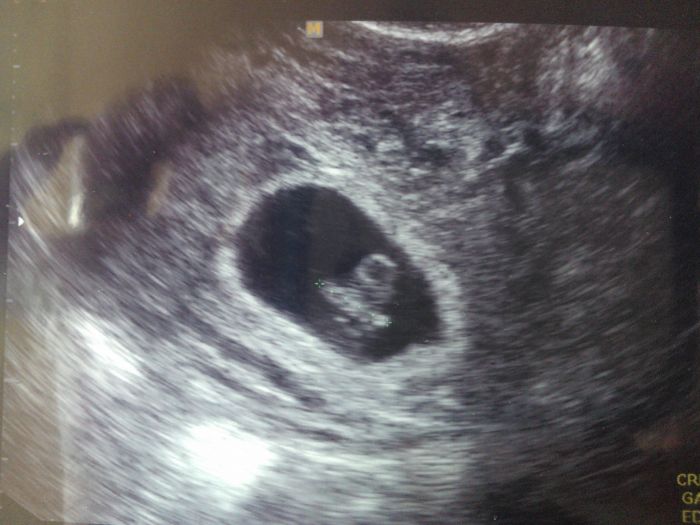

myslim na tebe zlato.... Jinak já jsem 7tt+6 dní podle MS, podle UTZ 7t+3 dny..... přikládám fotečku, mimi je tam kde je, roste.... příznaky nemám pořád žádné, jen mě bolí prsa, a chodim čurat pořád....Kajduško myslim moc moc na tebe, ted to vyjde, uvidis, za 9 dní máš na testu ducha

je uplně miniaturníííí, 10 mm mělo